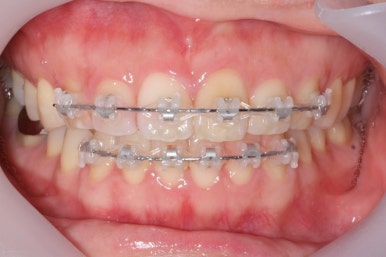

부산앞니교정 키다리아저씨치과에서 시행한 이번 MTA 부분교정의 전후 비교입니다.

위아래 앞니가 가지런해졌고, 작은 앞니의 얼룩무늬도 없어졌네요.

이상 부산앞니교정 키다리아저씨치과에서 결혼을 앞둔 예비신부를 MTA, 클리피씨 장치를 이용하여 부분교정을 한 치료사례였습니다.